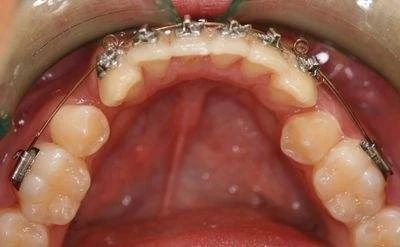

步骤四:分牙

用分牙圈套在上下左右的大牙之间,一般需要一周左右,目的是让牙齿移出一些空隙,好在戴牙套的时候能够放进固定牙套的钢圈。分牙时通常会感觉到牙齿酸软无力,上下牙齿碰到后可能会有点痛觉。